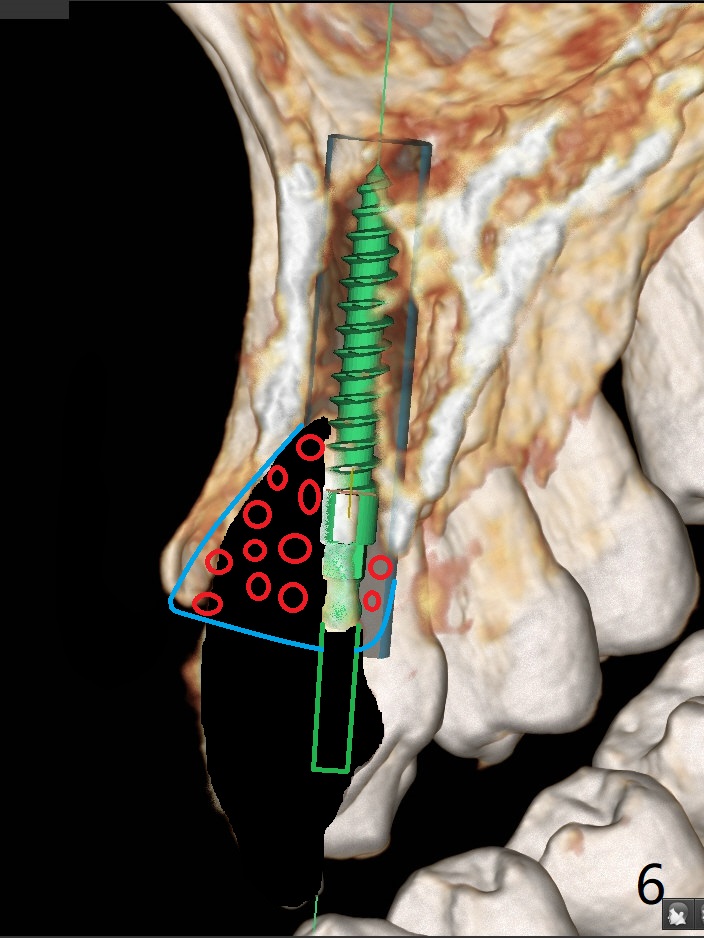

A 58-year-old man recently had sudden pain at #7 with labial plate loss (Fig.1 CT taken 3 years earlier). To avoid the labial placement of the large implants at #8, and 9, the implant at #7 will be smaller and palatally inserted (Fig.2). Fig.3 is a coronal section of 3D image of #7, showing the labial (B) and palatal (P) crests. After extraction (Fig.4 black), the narrow implant is placed between the crests (green). To repair the coronal labial plate, a piece of PRF membrane (Fig.5 blue) is placed inside the socket, followed by sticky bone (red circles). The portion of PRF membrane outside the socket will be flipped palatal, inserted into the abutment with a pre-punched hole and finally tucked underneath the palatal gingiva.